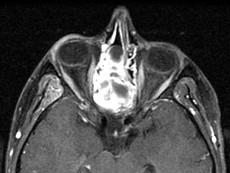

问题 15岁,男性,渐进性鼻塞1年余,MRI扫描如图所示,请选择最可能诊断()

选项 A.鼻咽部纤维血管瘤 B.鼻咽部脓肿 C.脊索瘤 D.鼻咽部囊肿 E.鼻咽癌

答案 A